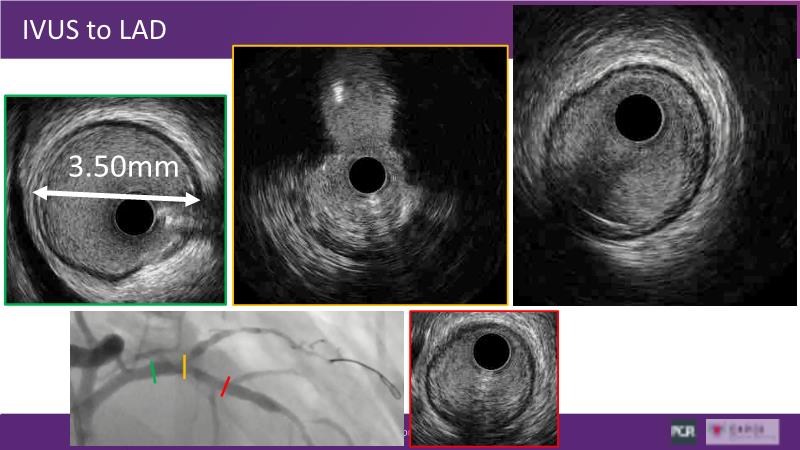

Through the study of two cases, this session examines the need for stenting bifurcation lesions and the role of DEB technology in avoiding stent-related complications in long diffuse disease. It emphasizes the benefits of SELUTION SLR balloons for de novo lesions, discussing how sustained limus release technology can broaden DEB indications and reduce metal usage, understanding the limitations of DES and the emerging role of DEB with sustained limus release, and learning how to identify dissections that can be left unstented.

- To discuss how sustained limus release technology can broaden DEB indications and reduce metal

- To understand the limitations of DES and the rationale and emerging role of DEB with sustained limus release